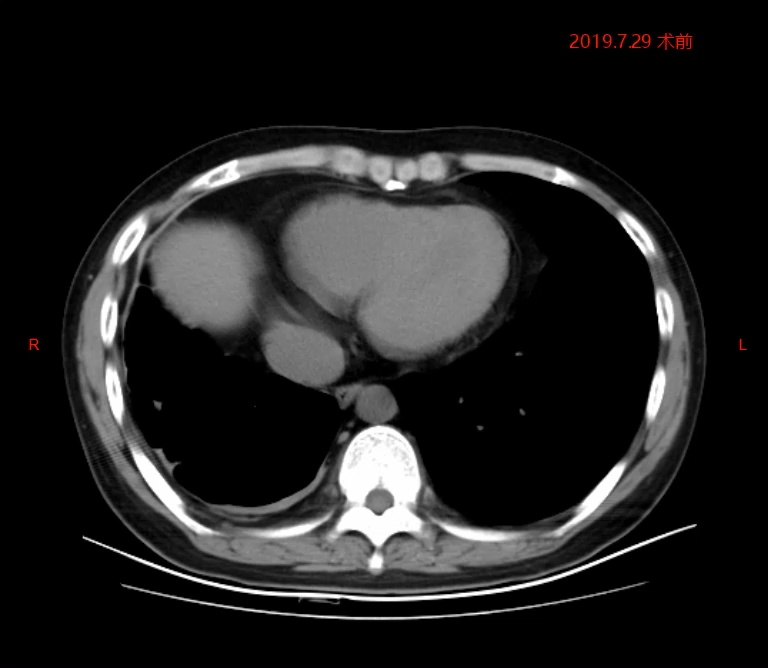

2019年7月术前检查

2019年7月术前检查